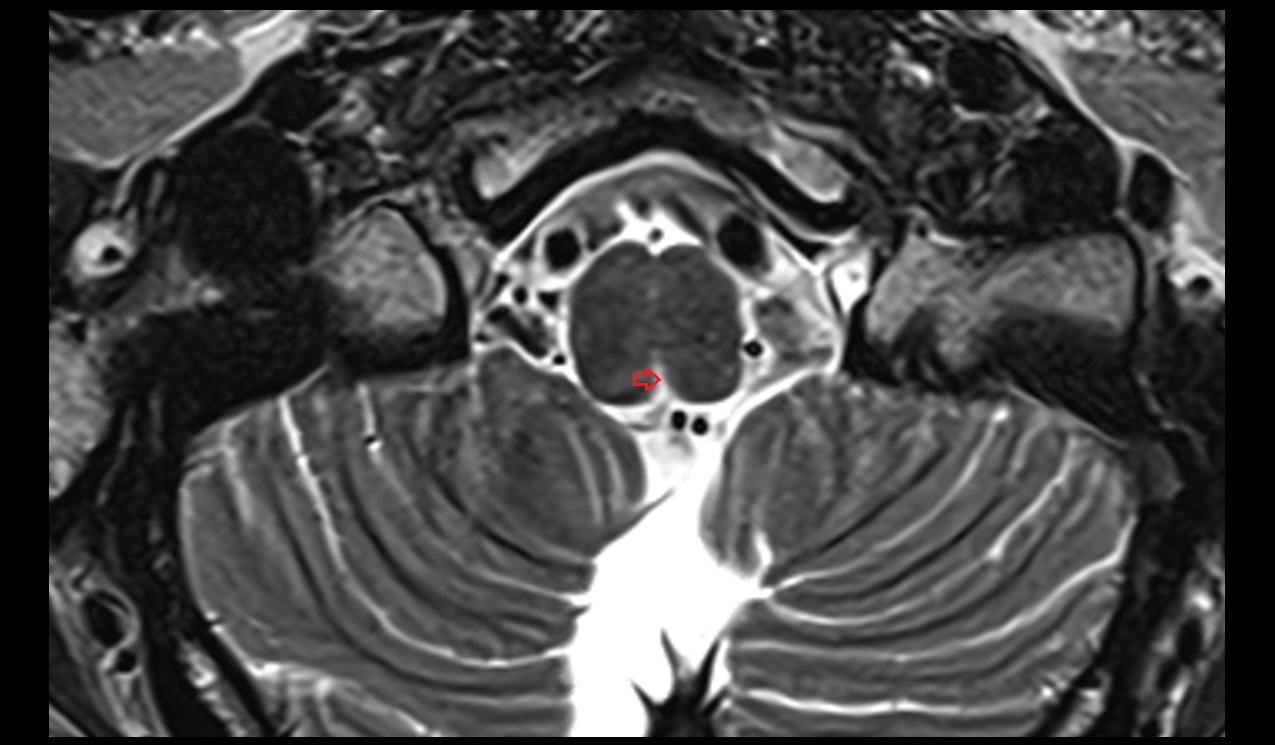

- Conus medullaris

- Cauda equina

- Spinal cord